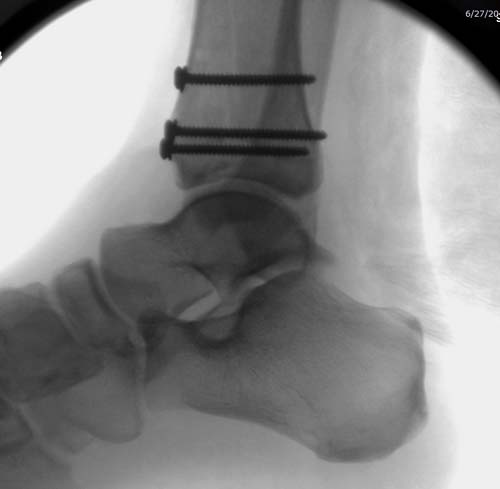

Первый случай, где перелом в результате падения с небольшой высоты, где мортиз рентген снимок показал отстутствие укорочения наружной

лодыжки и КТ срезы подсказали направления атаки. После такой фиксации нет надобности в гипсовой повязке, брейс и через две недели движения в

суставе без нагрузки.